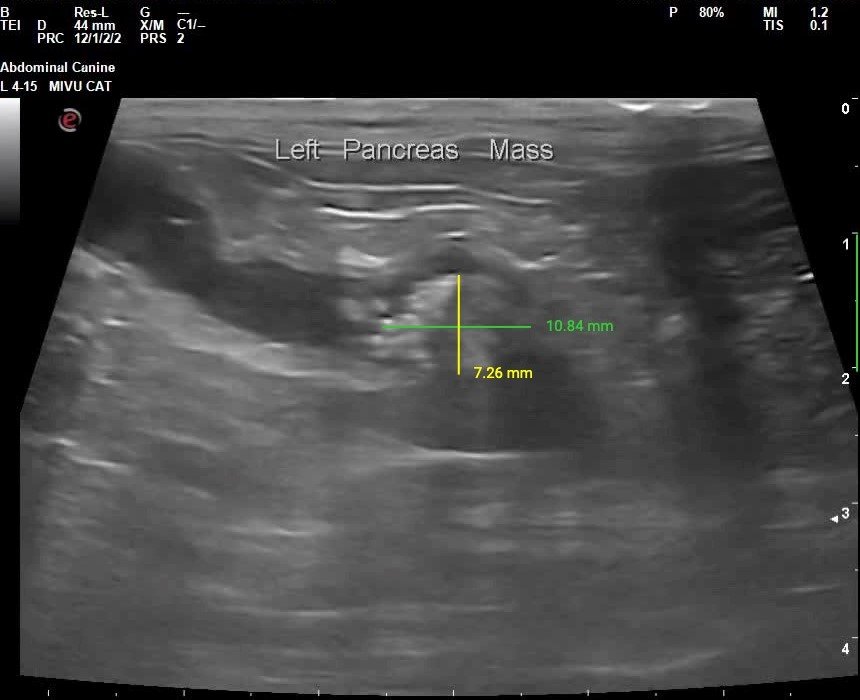

Pancreas: Enlarged size, deranged shape, and heterogeneous hypoechoic echogenicity. The pancreatic tissue is diminished due to diffuse severe pancreatic duct dilation, with a max dilation of approximately 1.0 cm. There appears to be an irregular crystalline severely hyperechoic calculus within the lumen of the distal left pancreatic duct measuring 1.1 x 0.7 cm, along with smaller mineral opacities throughout the pancreas. Peripancreatic fat is severely hyperechoic.

Image 1: Sagittal view of the distal left pancreas with mineralized structure(pancreaticolith) within the pancreatic duct.